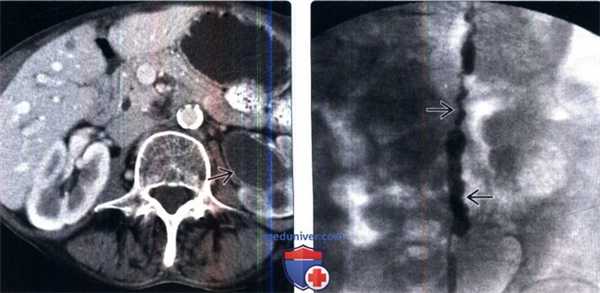

(Слева) Внутривенная пиелография в экскреторную фазу, прямая проекция: несколько пристеночных дефектов наполнения небольших размеров в левом мочеточнике, в проксимальном его отделе и в середине. Эти признаки характерны для кистозного уретерита.

(Справа) КТ-урография, реконструкция в плоскости наибольшей интенсивности, корональный срез: у пожилого мужчины с дизурией и предшествующими эпизодами инфекции вдоль правого мочеточника определяются несколько дефектов наполнения с ровным контуром На эндоскопии выявлено, что данные образования находятся в подслизистом слое, а в образцах биопсии отсутствовали признаки переходноклеточного рака.

(Слева) КТ с контрастированием, аксиальный срез: у пожилого мужчины с пиурией и лихорадкой определяется левосторонний гидронефроз и отсроченная нефрограмма. Стенки левого мочеточника и лоханки утолщены и накапливают контраст, что указывает на воспаление. На нефростомии был обнаружен пионефроз.

(Справа) Антеградная пиелография: у этого же пациента определяется неправильный контур левого мочеточника. Эти признаки характерны для уретерита. Спазм мочеточника может также играть роль у этого пациента, поскольку имеются признаки активной инфекции.